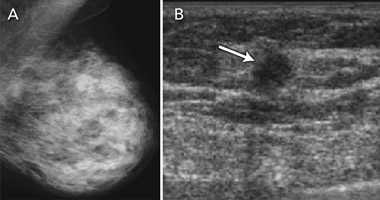

Breast ultrasound examination is not currently endorsed as a population-screening test, but has been applied in clinical practice for ad-hoc screening of women with dense breast tissue on mammography. Breast tissue density refers to the radiodense fibroglandular composition of the breast. High density of breast tissue is a significant and independent risk factor for breast cancer,23,24 and also reduces the sensitivity of mammography, as glandular tissue masks cancer on the mammogram. It is therefore not surprising that high density of breast tissue is associated with greater likelihood of an interval cancer in mammography screening,25 as women with dense breast tissue are both more likely to develop breast cancer and more likely to have cancer missed on mammography.

The accuracy of breast ultrasound examination is unaffected by breast tissue density. Ultrasonography has therefore been evaluated and applied in practice to “screen” women with dense breast tissue26-30 (Box 5). Evidence on its capacity to detect breast cancer in asymptomatic women with “negative” mammograms is summarised in Box 6. These studies provide data on additional (incremental) ultrasound detection — both true-positive and false-positive findings. The studies consistently show that ultrasonography is able to detect a substantial number of cancers in women with mammography-negative dense breast tissue, with additional cancers detected in 0.27%–0.46% of women screened with ultrasound.26-30 The detection capability of ultrasonography in this setting depends partly on how well mammography performs in the population being screened — “negative” mammograms may in fact show a cancer that has not been recognised by the screen-reader. This was demonstrated in a 2008 study that included “blinded” evaluation of the mammograms for ultrasound-only-detected cancers: about a quarter of ultrasound-detected cancers were perceived on the mammogram by an experienced radiologist.29 Another study found that the highest proportion of ultrasound-only-detected cancers (0.46%) occurred in women screened on the basis of dense breasts plus additional risk factors, with more than half of the screened women having a personal history of breast cancer.30 The false-positive rate for ultrasonography is considerable and varies between studies. False-positive results (in terms of both additional investigation and unnecessary surgical intervention) are the main potential limitation of ultrasonography in adjunct population screening.

The data in Box 6 also indicate that ultrasonography was able to detect breast cancers that were not identified in dense breasts on mammography screening at an early stage, generally at a comparable or earlier stage than cancers detected on mammography. This suggests that ultrasonography as an adjunct screening test may provide further benefit in screening women with dense breast tissue. It would thus be valuable to conduct large-scale RCTs of ultrasonography as an adjunct to mammography in screening women with dense breasts, with 2–3-year follow-up, to measure its impact on interval cancer rates. Demonstrating a reduction in interval cancers in women who have adjunct screening (relative to women who have mammography screening only) provides a surrogate indicator of longer-term benefit.11